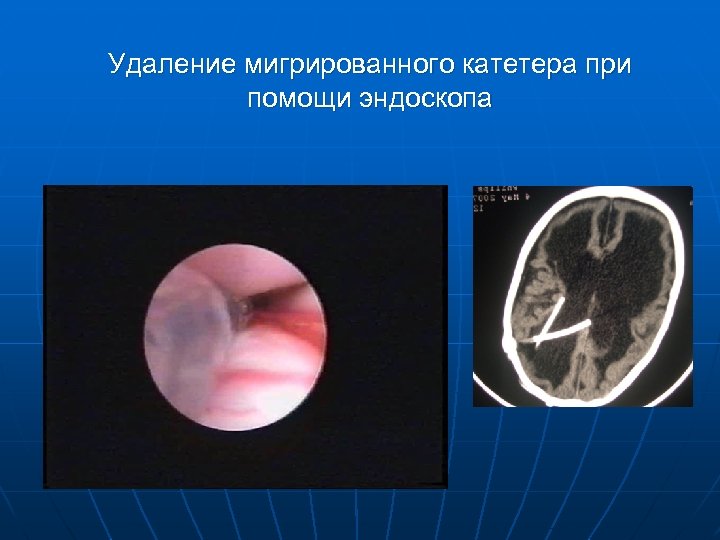

Удаление мигрированного катетера при помощи эндоскопа